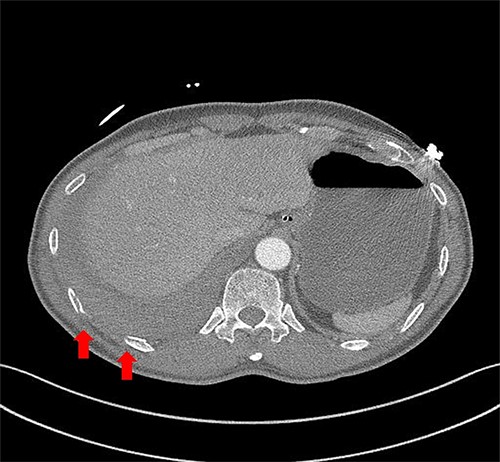

A 59-year-old man was admitted with multiple rib fractures and liver contusion due to a fall injury. He was standing on a chair for working at a farm, and it was knocked over causing him to fall and hit his flank against the corner of the chair. There was continuous pain while resting at the right flank and severe pain with pressure was noted, but no external wounds or bruises were observed. There were right 7th–11th rib fractures, scanty pneumothorax, minimal hemothorax and a 2-cm-sized liver contusion in abdomen and chest computed tomography (CT) scan (Fig. 1A, B). He was hospitalized for pain control and close observation in the general ward, and conservative management was initiated. Also, no significant changes were noted in the following daily follow-up chest radiographs. The patient suddenly complained of right-sided chest and back pain aggravation, cold sweating and fatigue 80 h after the traumatic injury. His mental status was alert, but v/s including systolic blood pressure (SBP) of 100–120 mmHg, heart rate (HR) of 40-60 beats/min and oxygen saturation of 100% during the admission changed to an SBP of 86/60 mmHg, HR of 88 beats/min and oxygen saturation of 97% when the symptoms occurred. Chest radiography was performed after the patient experienced aggravated symptoms, such as right-sided flank pain, cold sweating and fatigue. Compared to the previous scans, signs of increased opacification and peribronchial and parenchymal infiltrations were observed, which were indicative of hemothorax (Fig. 2A, B). We performed enhanced dynamic chest CT to identify any presence of active bleeding. On the chest CT scan, a large amount of hemothorax was identified in the right lung field along with multiple fractures of the right ribs. However, there were no signs of contrast leakage indicative of active bleeding (Fig. 3). Hemoglobin levels decreased from 13.1 g/dl on the day before the symptoms appeared to 11.5 g/dl at the onset of symptoms and to 9.4 g/dl after 2 h. Four packs of RBC transfusion and fluid were administered to the patient, and he was moved to the intensive care unit for close monitoring. And tube thoracostomy was performed, and 1600 ml of fresh blood was drained (Fig. 4A). The following day, 500 ml of blood was drained through the chest tube, but his v/s were stable (Fig. 4B). The amount of bleeding through the chest tube was decreased, but the drained fluid was fresh blood. And we thought that the remaining hematoma was not effectively drained, so the patient’s respiratory discomfort could persist and cause uneffective ventilation. And then we consulted with the Department of Thoracic Surgery, and video-assisted thoracoscopic surgery (VATS) exploratory thoracotomy was performed to identify the bleeding source caused by displaced rib and evacuate the large amount of hematoma. There was a large volume of hematoma within the pleural space and between the right lower lobe, diaphragm and fissure, but no active bleeding point was located. The fractured right 10th rib pierced through the pleural space and was displaced to the thoracic cavity, which was easily reduced. There was no injury surrounding the diaphragm, and although the general lung and chest wall contusions were severe, there were no signs of lung parenchymal lacerations (Fig. 5A–C). Chest tube drainage was serous, and there was no further bleeding. There were no signs of bleeding or any other abnormal findings on chest CT performed at the outpatient clinic, and the patient had no complaints of any symptoms (Fig. 6A, B).

Chest contrast-enhanced CT showed massive hemothorax with multiple rib fractures including 10th, 11th ribs (arrow) with no active extravasation of contrast.